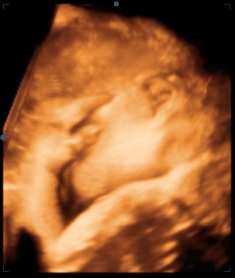

Со развојот на ултразвучната технологија и гинеколошкото ехо доживеа значајни промени. Воведувањето на тродимензионалното ехо донесе значајно подобрување на сликата на плодот при прегледот. Тродимензионална слика кај овие апарати се добива со регистрирање на поголем број пресеци и нивно компјутерско обработување во еден графички тродимензионален приказ. Резултатот од испитувањето на 3D ехо е слика која прикажува широчина, височина и длабочина на набљудуваната структура. Со поврзување на повеќе вакви слики во секвенца се добива 4D ултразвучен приказ (уште наречен динамичко 3D – 3D Live). Притоа се добива слика на лицето на бебето, се гледа како тоа го цица прстот, како се смее и слично.

3D технологијата има големо значење во интимното поврзување на мајката и бебето уште пред раѓањето. Исто така 3D ехото претставува уште една алатка во рацете на докторот која му овозможува уште подобар преглед на бебето во текот на бременоста. Со тродимезионалното ехо појасно се визуелизираат дефектите на горната усна (т.н. зајачка уста), дефектите на невралната цевка (спина бифида), полидактилијата (прекуброен прст), деформациите на стапалата на фетусот во текот на бременоста и слично.